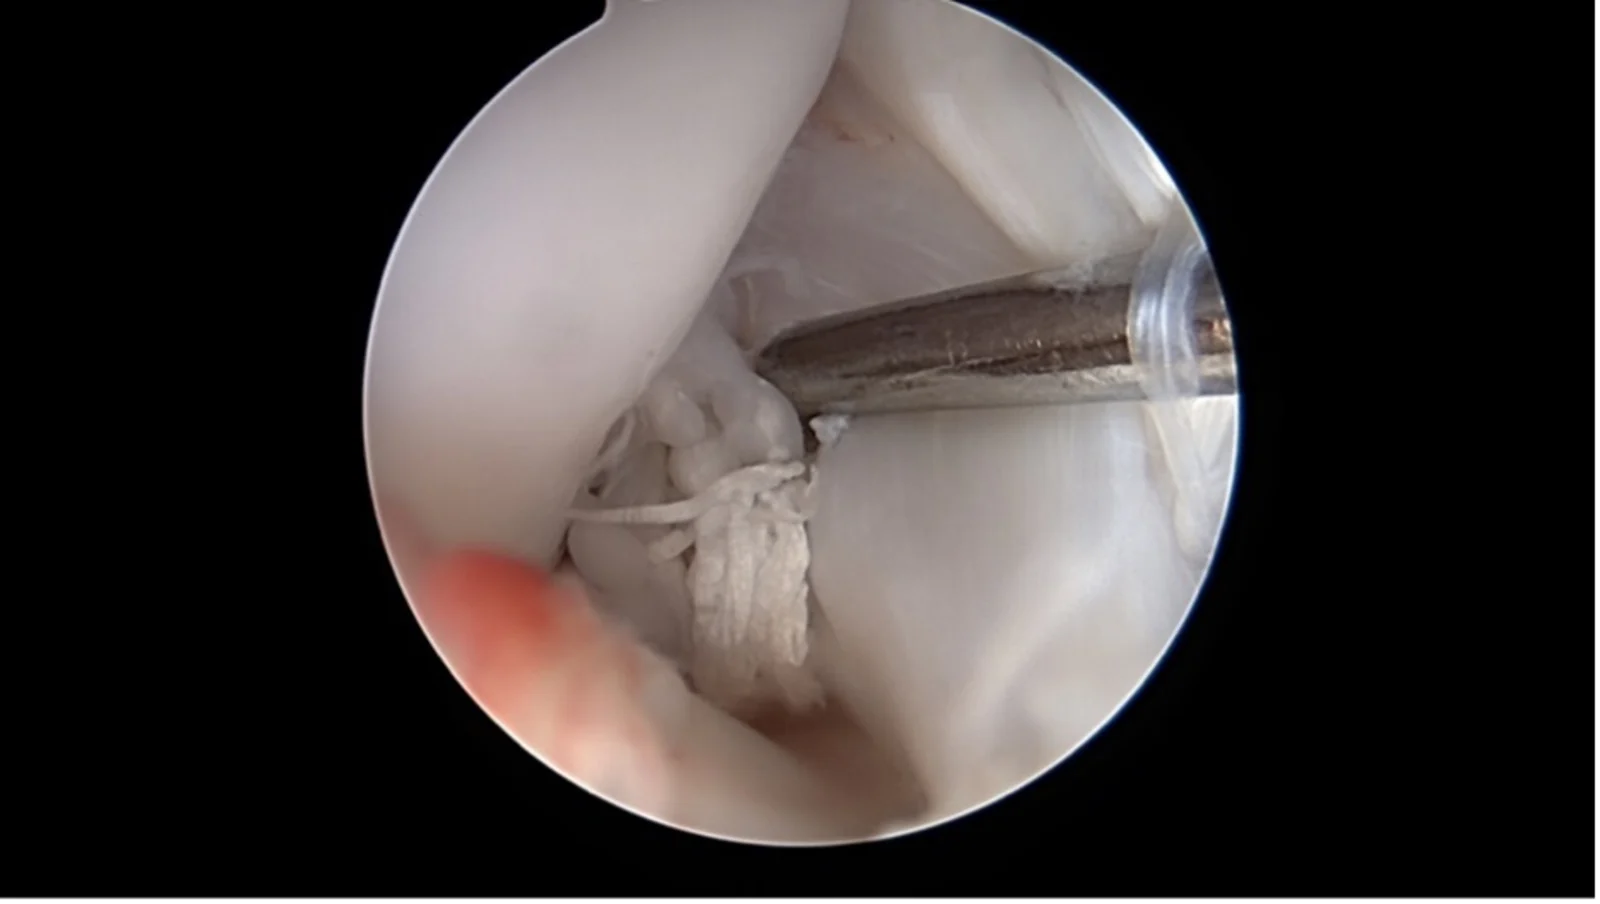

Arthroscopie

Une caméra miniaturisée permet de visualiser directement l’intérieur de l’articulation par de petites incisions cutanées. Les lésions du ligament croisé et les dommages associés comme les déchirures du ménisque peuvent être diagnostiqués et souvent traités immédiatement.

Rupture méniscale en anse de panier